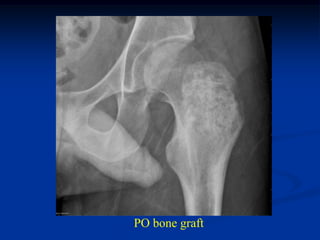

Case #636.1             Chondroblastoma with ABC

21 yr male with left hip pain for 4 mos.

Axial CT

scans

Cor PD   Gad

Axial T-1               T-2

T-2   Gad

PO bone graft